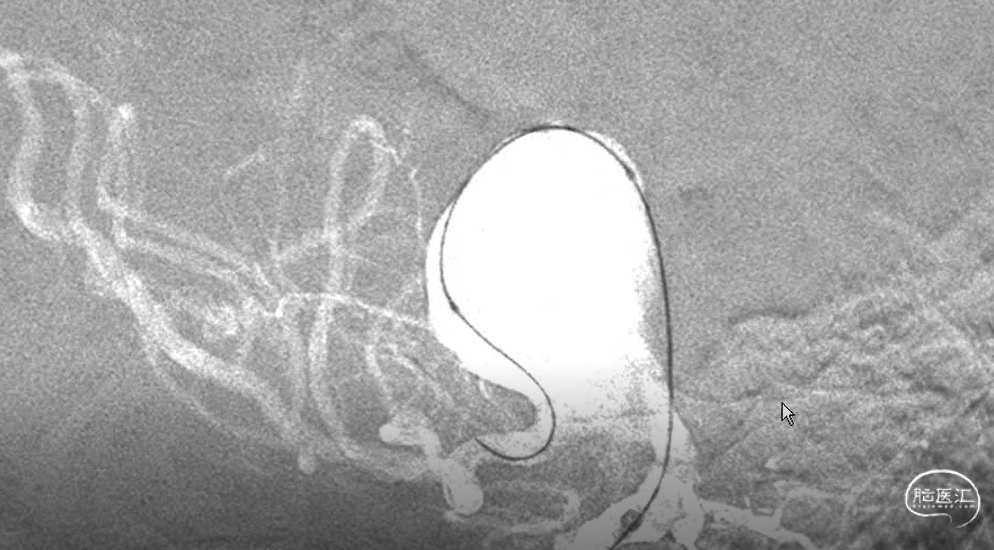

密网支架到位。

支架放到小弯侧缓慢是否,放置支架突入瘤内更多。同时放置远端支架调入动脉瘤内。

支架是否完毕,瘤内造影滞留。

术后效果还可以。

由于血管比较迂曲,支架贴壁性还可以。术后给与抗血小板治疗,小心翼翼度过一宿,时刻准备着是否有闭塞,和破裂的风险。好在一夜平安。